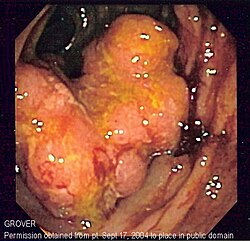

Endoskopski prikaz kolitisa u Crohnovoj bolesti na kojem se uočava difuzni gubitak normalne građe sluznice, nepravilna površina i eksudat.